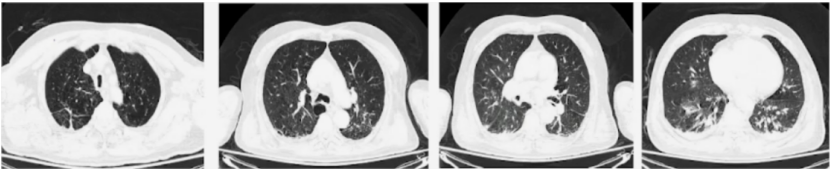

8月4日胸部CT:两肺多发实性小结节(多于10枚),直径均<5 mm;两肺肺气肿伴多发肺大泡形成;两肺散在陈旧灶(图1)

图片

图1  患者胸部CT(8月4日)